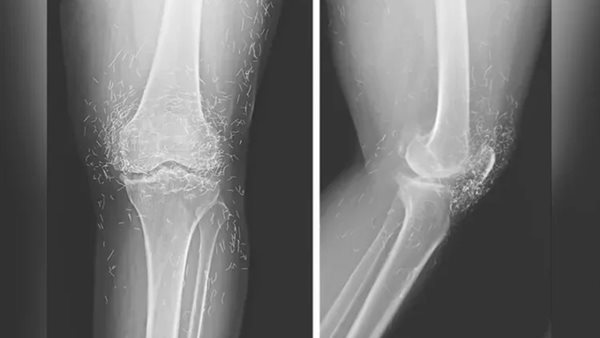

كشف فحص الأشعة السينية عن سماكة وتصلب في الجزء الداخلي من قصبة الساق، ونمو عظمي في الركبة، وجميعها أعراض شائعة لهشاشة العظام، بالإضافة إلى مئات من خيوط الذهب الصغيرة المغروسة في الأنسجة المحيطة بالركبة.